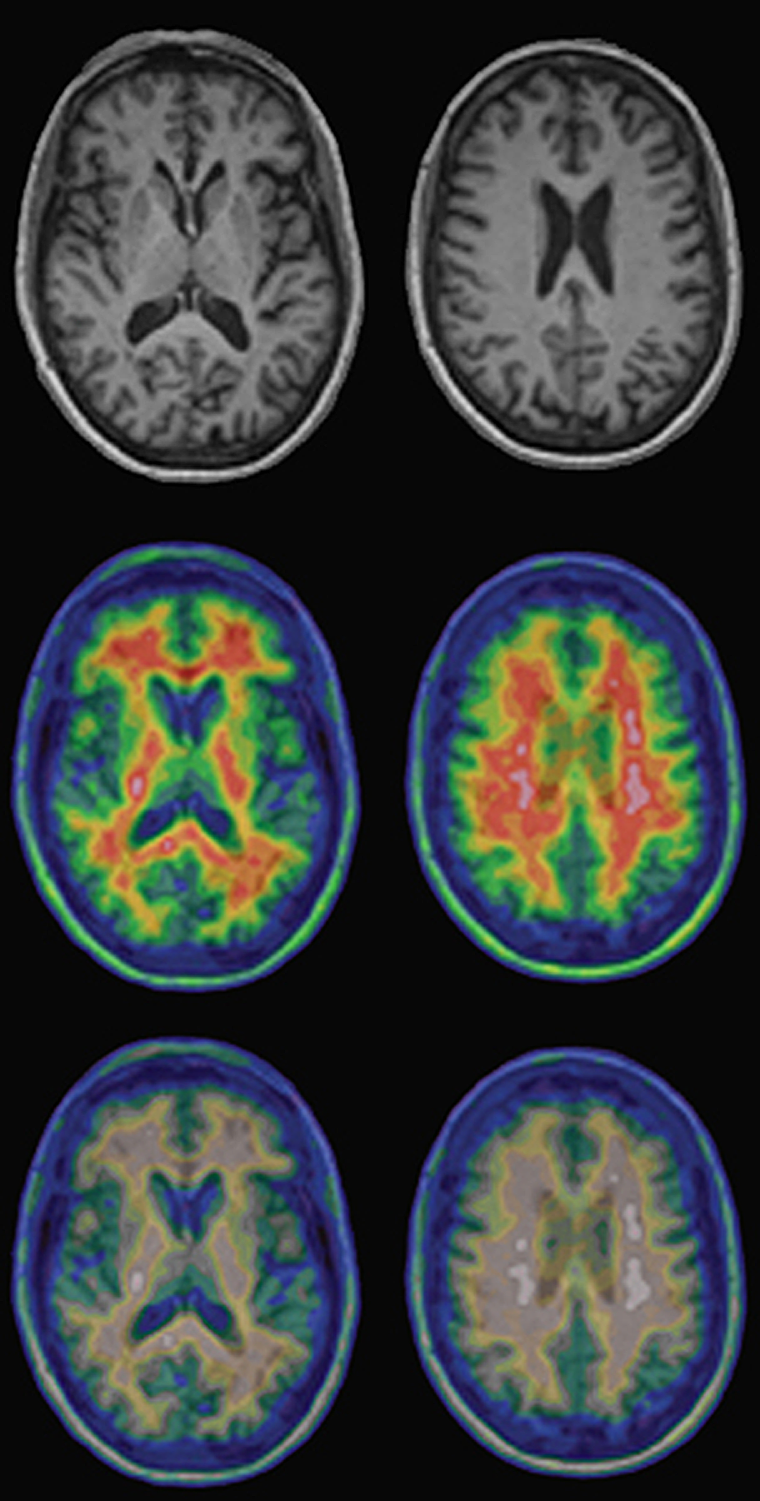

Figura 15-03:

Top:Regular T1-weighted gray-scale MR images of a healthy volunteer.

Center and bottom: PET-MRI fusion images of the same per­son. The upper row of the pseudo-color ima­­ges shows the normal images; the lower row shows the same ima­ges as seen by a person with red-green deficiency (deu­ter­ano­maly).